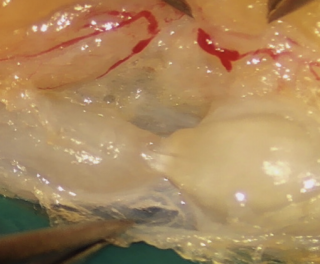

A 43-year-old high-level rock climber suffered a displaced fracture of the middle third of the scaphoid. The pre-operative ct scan revealed a bone cyst in the distal part of the scaphoid (Figure 1A). Due to this cyst, the retrograde Herbert like screw was inserted close to the palmar cortex to have the best hold in the bone (Figure 1B). Fracture healing was achieved after 6 weeks and the post-operative follow up remained unremarkable without any patient complaint. Two years later during an inverted grip in climbing (finger and thumb flexion with wrist hyperextension), the patient experienced a rupture of the FPL tendon due to palmar overhand. The palmar radiocarpal joint capsule was perforated (Figure 2). The screw protruding from the palmar surface of the scaphoid was removed. The FPL rupture was oblique and acute in appearance. Contact between the two stumps was easy and did not induce excess flexion of the thumb, which is why we opted for a direct suture and not an intercalated graft. Direct suture of the FPL tendon was performed using the Lim-Tsai technique (Supramid) and reinforced with a Krakow suture (FiberWire).